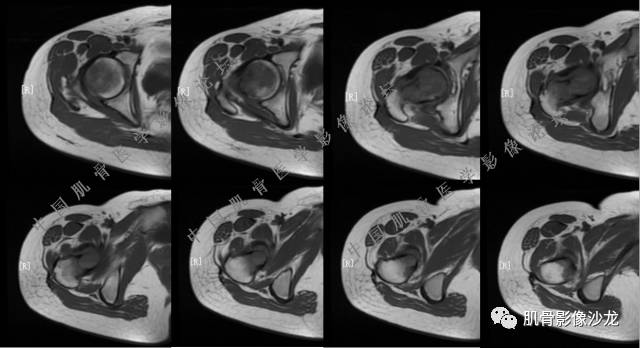

主诉:右大腿疼痛、活动受限20天

现病史:患者于20天前无明显诱因出现右下肢疼痛,活动受限,疼痛呈阵发性,活动后加重。自行口服止痛药芬必得,效果不佳,至当地医院治疗,检查发现右侧股骨近端病变。遂来诊

葛英霖 20:30 原发或继发动脉瘤样骨囊肿,继发于巨细胞瘤,软骨母,纤维组织细胞瘤,骨母等等

向以四 20:30 软骨母合并ABC,

医影在线 20:30 软骨母,/继发ABC

飞鹰行动 20:31 T2信号高,有软骨成分

Echo 20:32 T2确实有一块区域很亮 ,并有野液平

葛英霖 20:36 这不是良性病变

葛英霖 20:36 中间型可能性极大

葛英霖 20:37 明显侵蚀骨内膜啊,硬化边也不完整 (细箭头所示)

葛英霖 20:43 提不提也很明显继发了abc

Echo 20:44 葛老师~继发ABC是根据有液液平面判断么?

葛英霖 20:44 是

葛英霖 20:46 明显的多囊状改变,液液平面